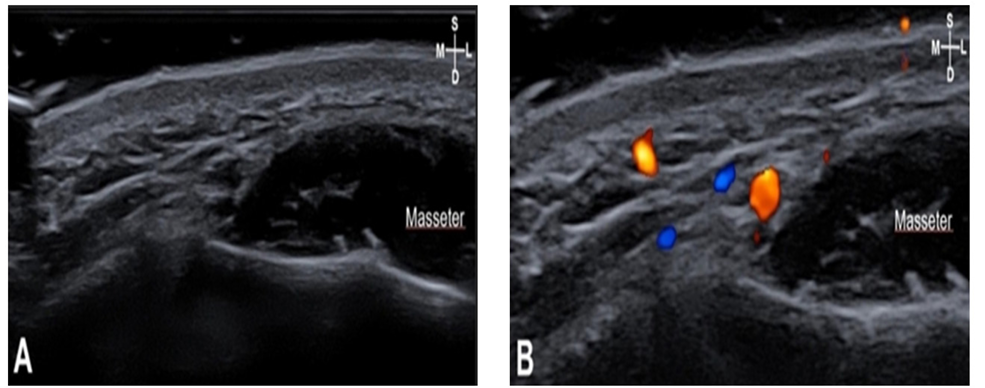

Depressor anguli oris muscles were observed in F2, and the depth from skin to depressor anguli oris muscles was 8.6±2.1 mm, and this muscle was observed in 90% of 40 cases. Orbicularis oris muscles were observed in F3 and F4 <Fig. 5,6>. The depth from skin to orbicularis oris muscles was 9.5±3.3 mm in F3 and 6.3±3.1 mm in F4, respectively <Table 2>.

Fig. 6. Sonography (A) and doppler image (B) of F4: Arterial depth of F4 is 4.9mm, skin to the orbicularis oris (OOr) depth is 6.3 mm. S: superficial; D: deep; M: medial; L: lateral; Yellow: facial artery; Blue: facial vein